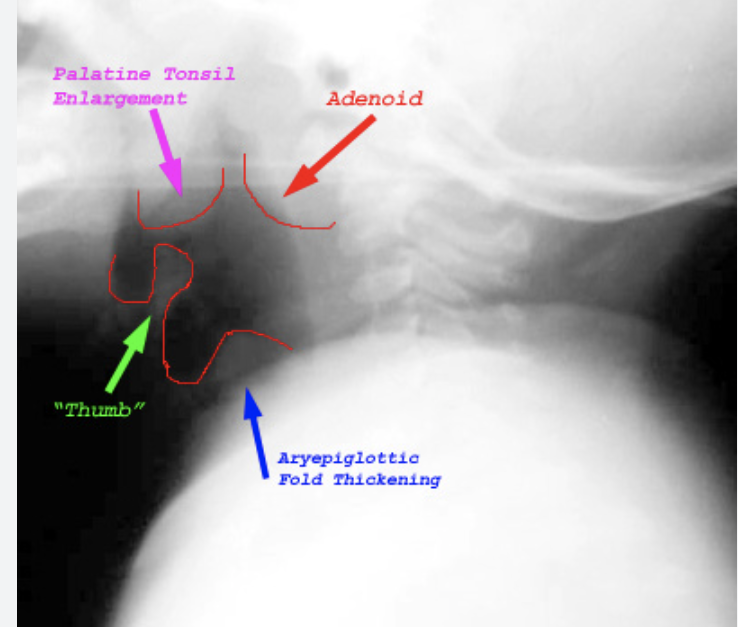

1 - Lateral neck radiograph (‘thumb sign’)

Flexible fiberoptic laryngoscopy (ENT only) will show a cherry red epiglottis